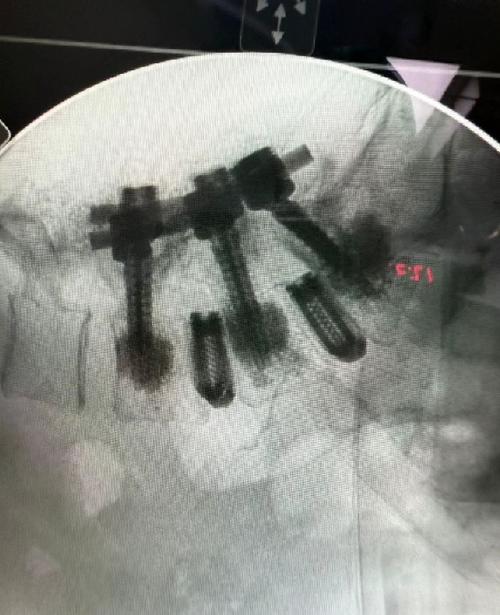

Como parte de su reaparición, Alejandra compartió una nueva fotografía de su más reciente resonancia magnética, donde se observan las piezas de titanio en su columna.

"Es increíble cómo me siento, estoy bien operada. Hay mucho más y vamos a seguir adelante, brillando y siendo felices. Los amo", concluye con alegría Guzmán, que, a pesar de no dar detalles médicos específicos, deja en claro que se encuentra estable.